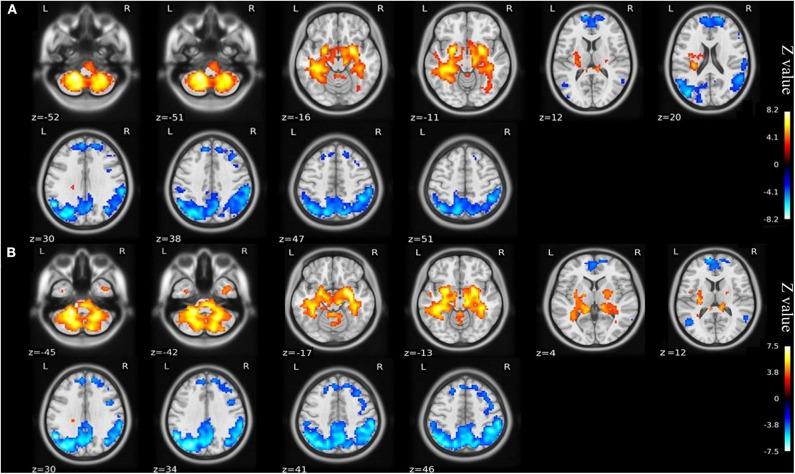

This study aimed to investigate the brain functional alterations with resting-state functional magnetic resonance imaging (rs-fMRI) in older patients with knee osteoarthritis (KOA) before and after total knee arthroplasty (TKA) and to assess the causal relationship of the brain function and neuropsychological changes. We performed rs-fMRI to investigate brain function of 23 patients aged ≥65 with KOA and 23 healthy matched controls. Of the KOA patients, 15 completed postoperative rs-fMRI examinations. Analyzes of the amplitude of low-frequency fluctuation (ALFF) and functional connectivity (FC) were used to estimate differences in brain functional parameters between KOA patients, postoperative patients, and the controls. The relationship between changes of pre- and post-surgical status in ALFF and neuropsychological test results was analyzed. Compared with the controls, all patients with KOA exhibited decreased ALFF in the default mode network (bilateral angular gyrus, precuneus gyrus, medial superior frontal gyrus) and increased ALFF in the bilateral amygdala and cerebellum posterior lobe before surgery ( < 0.001). Altered ALFF persisted in the same brain regions 1 week postoperatively. The decreased ALFF in the left precuneus gyrus and middle temporal gyrus was found after surgery when compared with preoperative data ( < 0.01). Preoperatively, the KOA patients exhibited increased FC between the left precuneus gyrus and the right supplementary motor area compared to the controls ( < 0.001), but this connectivity became no significant difference after TKA. The left Cerebelum_9 was found to have decreased FC with the right precuneus gyrus postoperatively ( < 0.001) although this was not significantly different before surgery. The significantly altered ALFF values were not correlated with changes in cognitive assessment scores. In older patients with end-stage KOA, functional alterations in important brain regions were detected with the persistence and further changes observed at an early stage after knee replacement. Our data further our understanding of brain functional abnormalities and cognitive impairment in older patients following knee replacement, which may provide therapeutic targets for preventive/treatment strategy to be developed. Clinical Trial Registration: http://www.chictr.org.cn/index.aspx, ChiCTR1800016437; Registered June 1, 2018.

本研究旨在通过静息态功能磁共振成像(rs-fMRI)调查老年膝骨关节炎(KOA)患者全膝关节置换术(TKA)前后的脑功能改变,并评估脑功能与神经心理变化之间的因果关系。我们对23例年龄≥65岁的KOA患者及23名匹配的健康对照者进行rs-fMRI以研究脑功能。其中15例KOA患者完成了术后rs-fMRI检查。采用低频振幅(ALFF)分析和功能连接(FC)分析来评估KOA患者、术后患者及对照者之间脑功能参数的差异。分析了手术前后ALFF变化与神经心理测试结果之间的关系。与对照组相比,所有KOA患者术前默认模式网络(双侧角回、楔前回、额上回中部)的ALFF均降低,双侧杏仁核和小脑后叶的ALFF增加(<0.001)。术后1周,相同脑区的ALFF改变持续存在。与术前数据相比,术后发现左侧楔前回和颞中回的ALFF降低(<0.01)。术前,与对照组相比,KOA患者左侧楔前回与右侧辅助运动区之间的FC增加(<0.001),但TKA术后这种连接性无显著差异。术后发现左侧小脑_9与右侧楔前回的FC降低(<0.001),尽管术前无显著差异。ALFF值的显著改变与认知评估评分的变化无关。在老年终末期KOA患者中,检测到重要脑区的功能改变,且在膝关节置换术后早期观察到这些改变持续存在并进一步变化。我们的数据进一步加深了我们对老年患者膝关节置换后脑功能异常和认知障碍的理解可能为制定预防/治疗策略提供治疗靶点。临床试验注册:http://www.chictr.org.cn/index.aspx,ChiCTR1800016437;2018年6月1日注册。